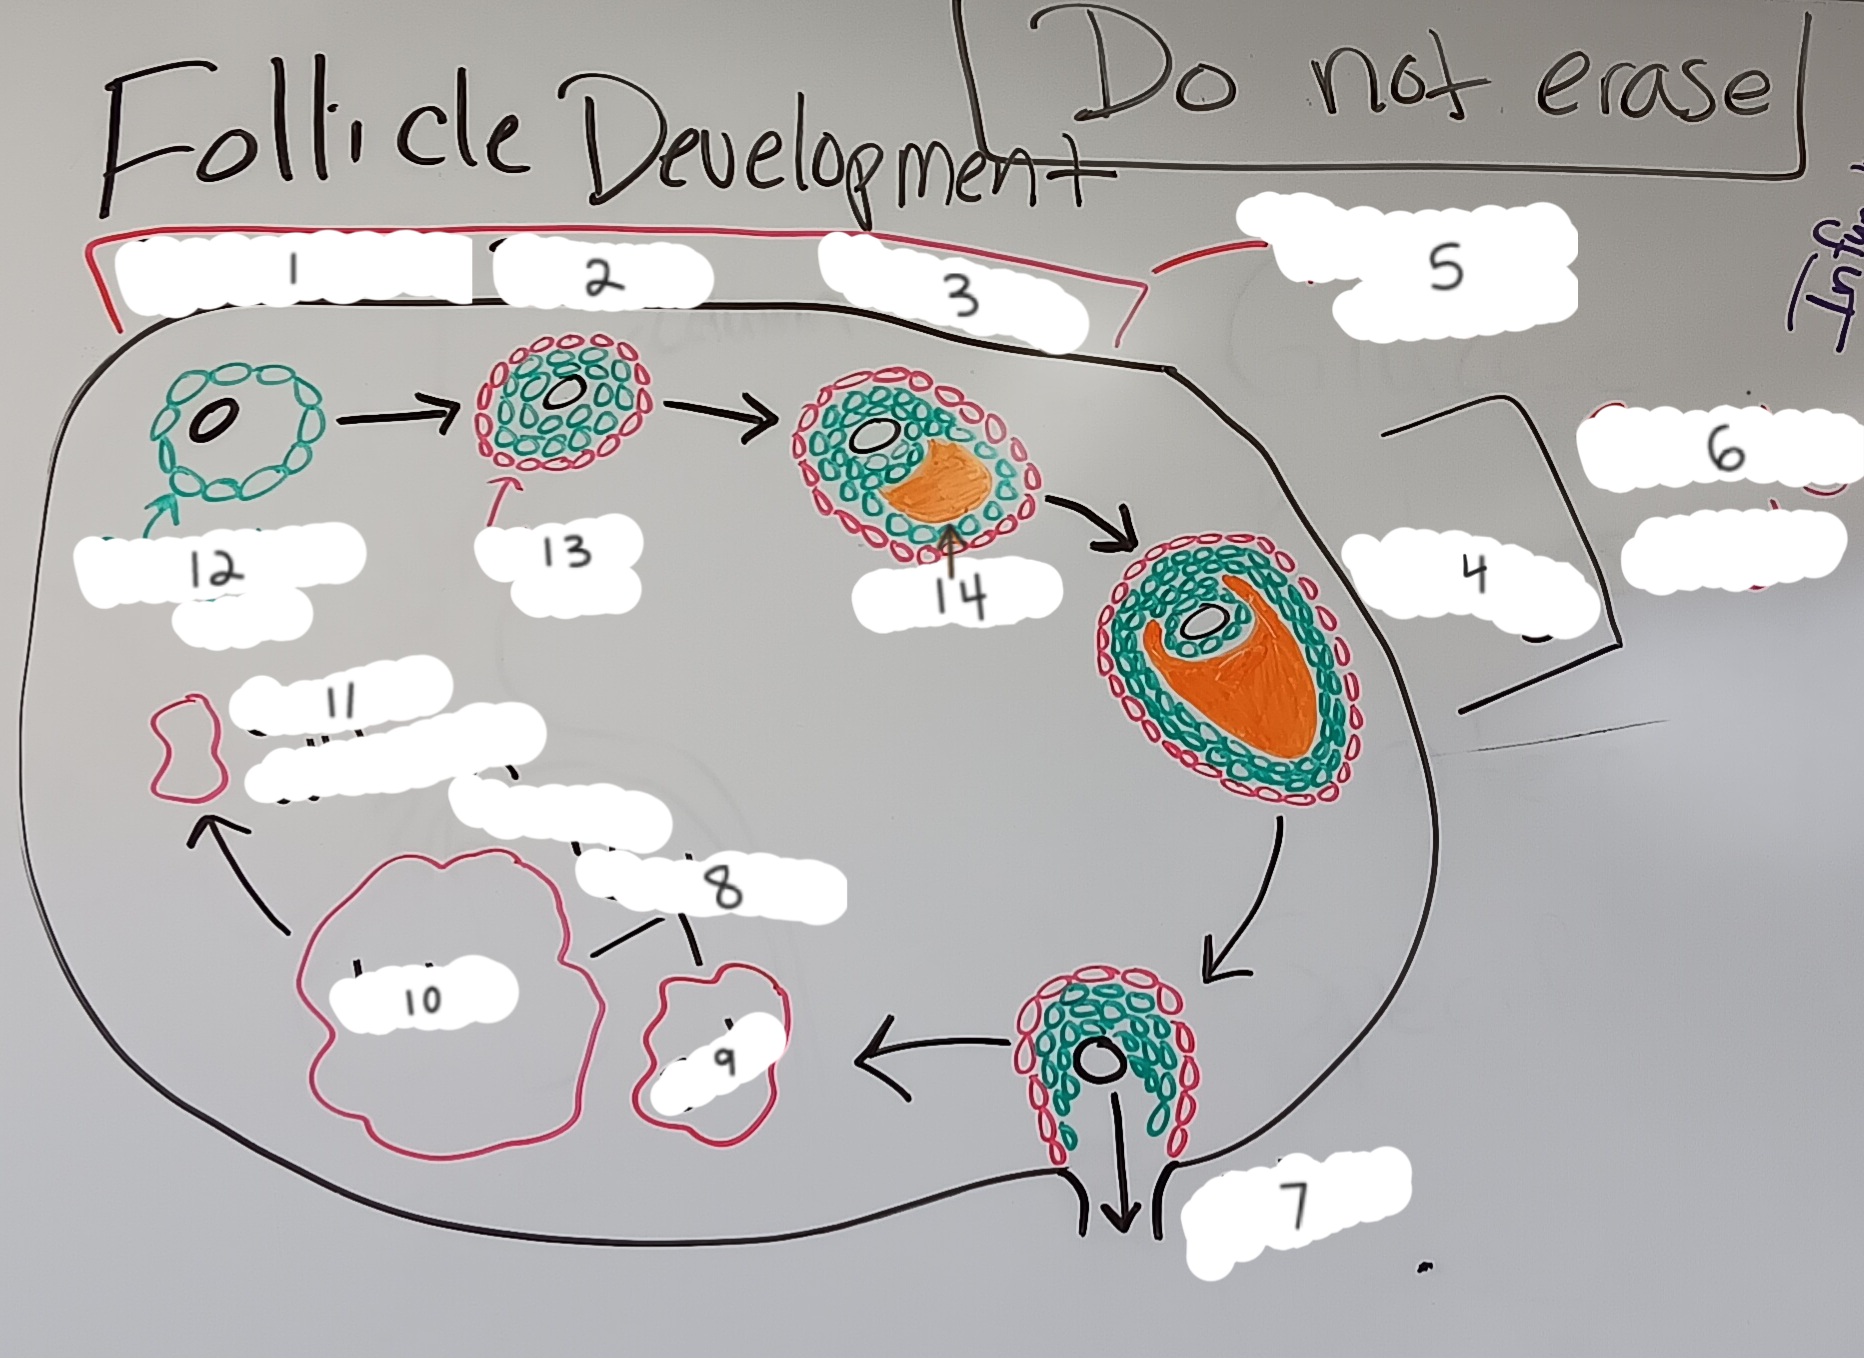

Oocyte

6 (the whole structure)

Primary oocyte

5

Secondary oocyte

6

Granulosa cell

7

Primordial follicle

1

Primordial follicle

Primordial follicle

1

Primary follicle

2

Primary follicle

Primary follicle

2

Secondary follicle

3

Secondary follicle

Secondary follicle

3

Tertiary follicle

4

Tertiary follicle

4

Mature follicle

5

Mature follicle

Mature follicle

7

Antrum

10

Zona pellucida

9

Theca folliculi

8

Corona radiata

Corpus luteum

Corpus luteum

Corpus albicans

Corpus albicans

corpus luteum

8

early corpus luteum

9

late corpus luteum

10

corpus albicans

11

granulosa cells

12

theca cells

13

antrum

14